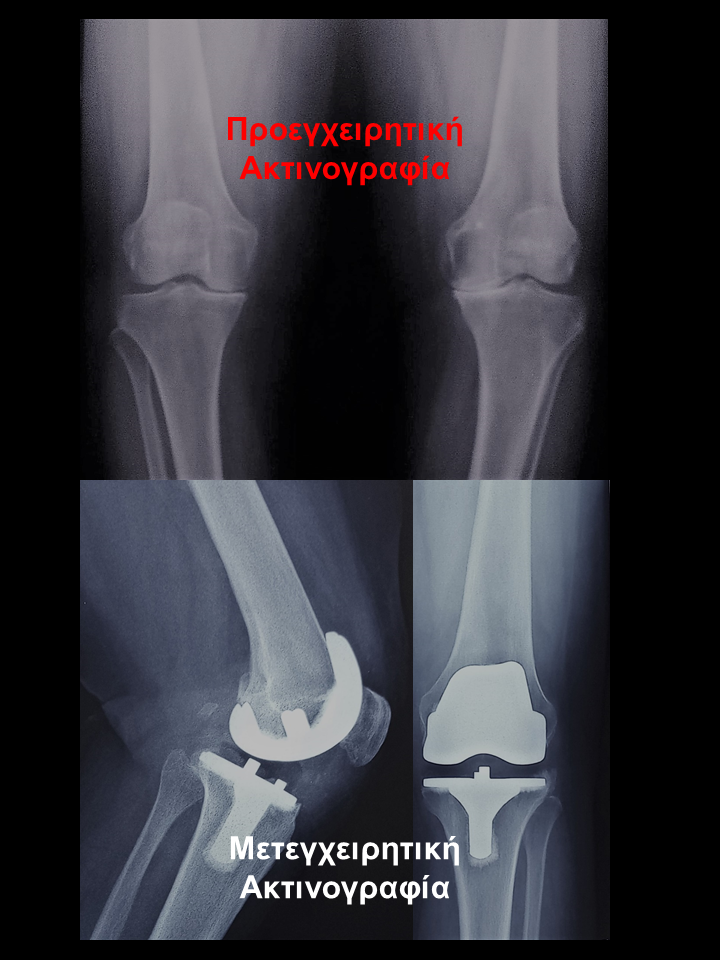

Ασθενής με οστεοαρθρίτιδα αριστερού γόνατος

Ασθενής 75 χρονών με οστεοαρθρίτιδα δεξιού γόνατος μεγάλη παραμόρφωση και αστάθεια. Είχε επιδεινούμενο άλγος δεξιού  γόνατος που την δυσκόλευε στη βάδιση, στο κάθισμα και την αφυπνούσε το βράδυ. Υπεβλήθη σε ρομποτική αρθροπλαστική γόνατος. Χρησιμοποιήθηκε η τεχνική διατήρησης οστού όπου αφαιρέθηκαν λιγότερα χιλιοστά οστού. Ο άξονας από 90 αποκαταστάθηκε στις 00 , η υπερέκταση  από 100 σε 40  και η κάμψη στις 990 . Η ασθενής βαδίζει πλέον χωρίς καμία ενόχληση.